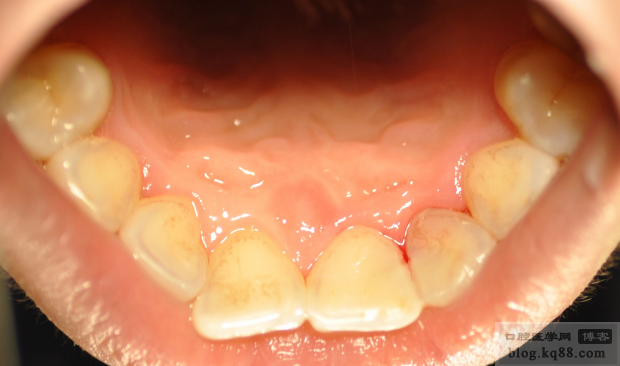

22根尖區(qū)陰影,但是該牙未見明顯不適,所以行一次性根管治療(插針片和根充片如下)

根充完成后取模

在模型上嵌體蠟恢復(fù)外形